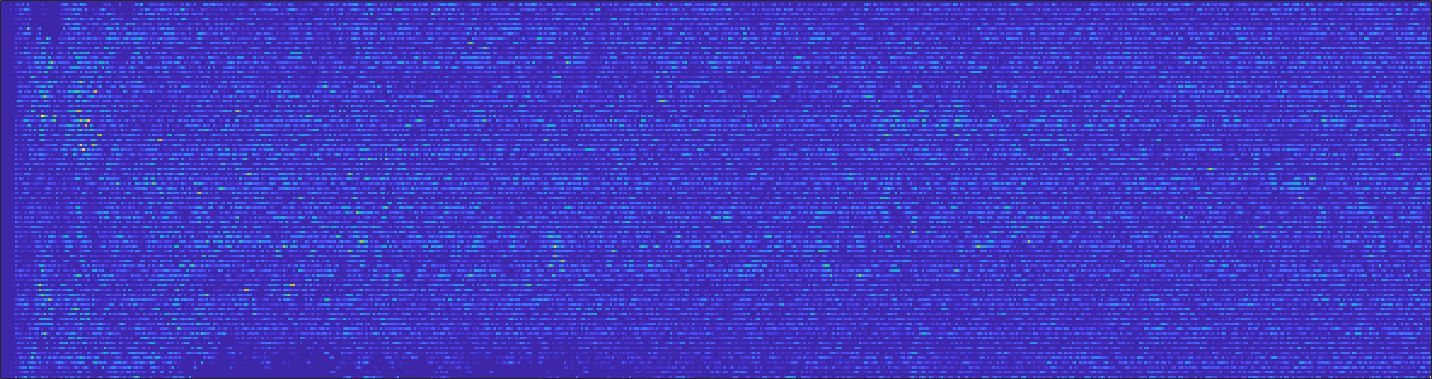

We train each learning-based network (custom-WDSR) with 1.5K images, where the input is the outcome of the selected up-sampling method (i.e., Cubic convolution), and the target is the original high-resolution image. Indeed, input and target images have the same resolution, as the reconstruction of the missing lines has been already performed by Cubic convolution. Figs. 3, 4, and 5 show the results of the network prediction, compared with the input and the target images. Target images correspond to spatial high-resolution images; input images are the outcome of the up-sampling interpolation, which is applied to spatial low-resolution images (i.e., the down-sampling along the lateral direction of high-resolution images); prediction images represent the output of the neural network.

Our framework visually improves the results, in terms of blurring and artefacts. This result is more evident in the magnification of the ear of the foetus (Fig. 3), the mitral valve (Fig. 4), and the mass edges (Fig. 5). Fig. 6 shows the error image of the three anatomical districts with both 2X and 4X up-sampling factors, with the maximum error in the scale . The error is more evident in the contours of the anatomical structures; moreover, the abdominal district shows a smaller error than the cardiac and obstetric ones. We underline that the view for each image is scaled to its maximum, to improve the visualisation of the error.

Fig. 7(a-b-c, left) shows the box plot of the statistics of the PSNR on three different anatomical districts, comparing the target images with the prediction and the cubic convolution, respectively. The metrics are computed on a data set of 200 images of the same district and with the same up-sampling factor. We report that the PSNR median value improves of on obstetric 2X raw images, on cardiac 2X raw images, and on abdominal raw 4X images.

Fig. 7(a-b-c, right) shows the histogram of the absolute value of the error with respect to the target image, of the prediction and Cubic convolution results, respectively. The histograms show the number of pixels where the prediction error is lower than 5 (i.e., the first bin of the histogram), which means very similar to the target when visually analysing the images. From the Cubic convolution to the predicted images, this value increases of on obstetric 4X raw images, on cardiac 4X raw images, and on abdominal 4X raw images.

Fig. 8 shows the box plot of the SSIM (a-b-c, left) and MAE (a-b-c, right) quantitative metrics, as performed for PSNR metric. Also, these metrics show that our method improves the results of Cubic convolution both in terms of average value and variability. For example, the SSIM median value improves of on obstetric 4X images and the MAE median value improves of on cardiac 2X images.